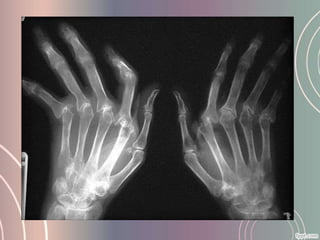

• Artritis                                                reumatoidea

Esta enfermedad articular es una forma común de artritis crónica que

causa inflamación en el revestimiento de las articulaciones

(membrana sinovial) con dolor, rigidez, deformidad y limitación de los

movimientos.

La enfermedad progresa en tres etapas. La primera etapa es la

inflamación de la membrana sinovial lo que causa dolor, calor,

rigidez, enrojecimiento e hinchazón alrededor de la articulación. En

una segunda etapa existe una división rápida y crecimiento de las

células de la membrana sinovial ocasionando un engrosamiento de

la misma (esto es llamado panus) lo que forma un tejido anormal en

la articulación. En la última etapa estas células inflamadas secretan

enzimas que dañan al hueso y cartílago dando como consecuencia

deformidad, más dolor y pérdida del movimiento de dicha

articulación.

• Cómo se diagnostica?

• Exploración de la zona: hinchazón, alta temperatura,

enrojecimiento de la piel, rigidez y movimiento limitado.

• Análisis de sangre: la presencia del factor reumatoide,

anemia, elevada tasa de sedimentación de eritrocitos y

de proteína activa C ayudan al diagnóstico de la artritis

reumatoidea ya que indican inflamación.

• Radiografías    convencionales:        son  un      método

diagnostico a tener en cuenta

• Técnicas más complejas : gammagrafía ósea, la

densitometría ósea y la resonancia magnética nuclear y

ultrasonido          de             la         articulación